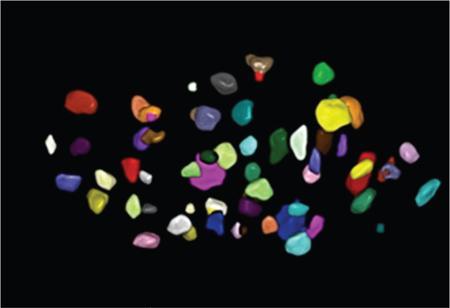

• Complete view of all follicles within volume by inversion method (Fig. 11.20.1.4).

4. 4. Sono automated volume calculation (AVC) – semiautomatic method (Fig. 11.20.1.5).

• Measured using software

• Counts and measures all follicles

• Lesser scan time

• Twenty follicles are at least required for visual advantage

• Correction of problems is frequently required by manual postprocessing, for example, to include follicles which have not been identified and to exclude other extraovarian structures or tissues which are incorrectly identified as follicles (e.g. hydrosalpinx, Morgagni cysts).

• Requires specifically trained radiologists and specific ultrasound systems

Image

Fig. 11.20.1.4 Inversion mode.

Fig. 11.20.1.5 Sono AVC.